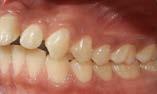

Las lesiones traumáticas de los dientes permanentes son comunes y afectan entre el 10.5% y el 17.3%. La extrusión, la luxación lateral y la intrusión se encuentran entre los tipos más graves de traumatismo dental que pueden alterar el suministro vascular a la pulpa. Radiográficamente, las partes apical y lateral del alvéolo parecen vacías y, en general, el espacio del ligamento periodontal está agrandado. La obliteración del canal pulpar (OCP) y la necrosis pulpar (NP) son las consecuencias más frecuentes de la luxación extrusiva, mientras que la reabsorción radicular (RR) es menos frecuente. Las complicaciones dependen de factores como la gravedad de la lesión, el estadio de desarrollo radicular y la presencia de una alta carga bacteriana bucal. Las complicaciones pulpares y periodontales son más frecuentes en dientes con raíces completamente formadas que en ápice abierto. La prevalencia de obliteración del canal pulpar (OCP) como consecuencia de lesiones por avulsión y luxación está entre el 3 y el 24%. Por el contrario, es muy poco probable que los dientes con ápice cerrado presenten revascularización y a menudo desarrollan

Figura 2. Imagen representativa de una luxación extrusiva en el órgano dental 11 que presenta un cambio de coloración en la encía.

necrosis pulpar. Las lesiones por luxación extrusiva requieren un tratamiento inmediato, consistente en reposicionamiento y estabilización. El tratamiento comienza con un correcto diagnóstico clínico y radiográfico, seguido del reposicionamiento manual del diente en el alvéolo y la colocación de una férula flexible, para permanecer in situ durante aproximadamente 2 semanas.6